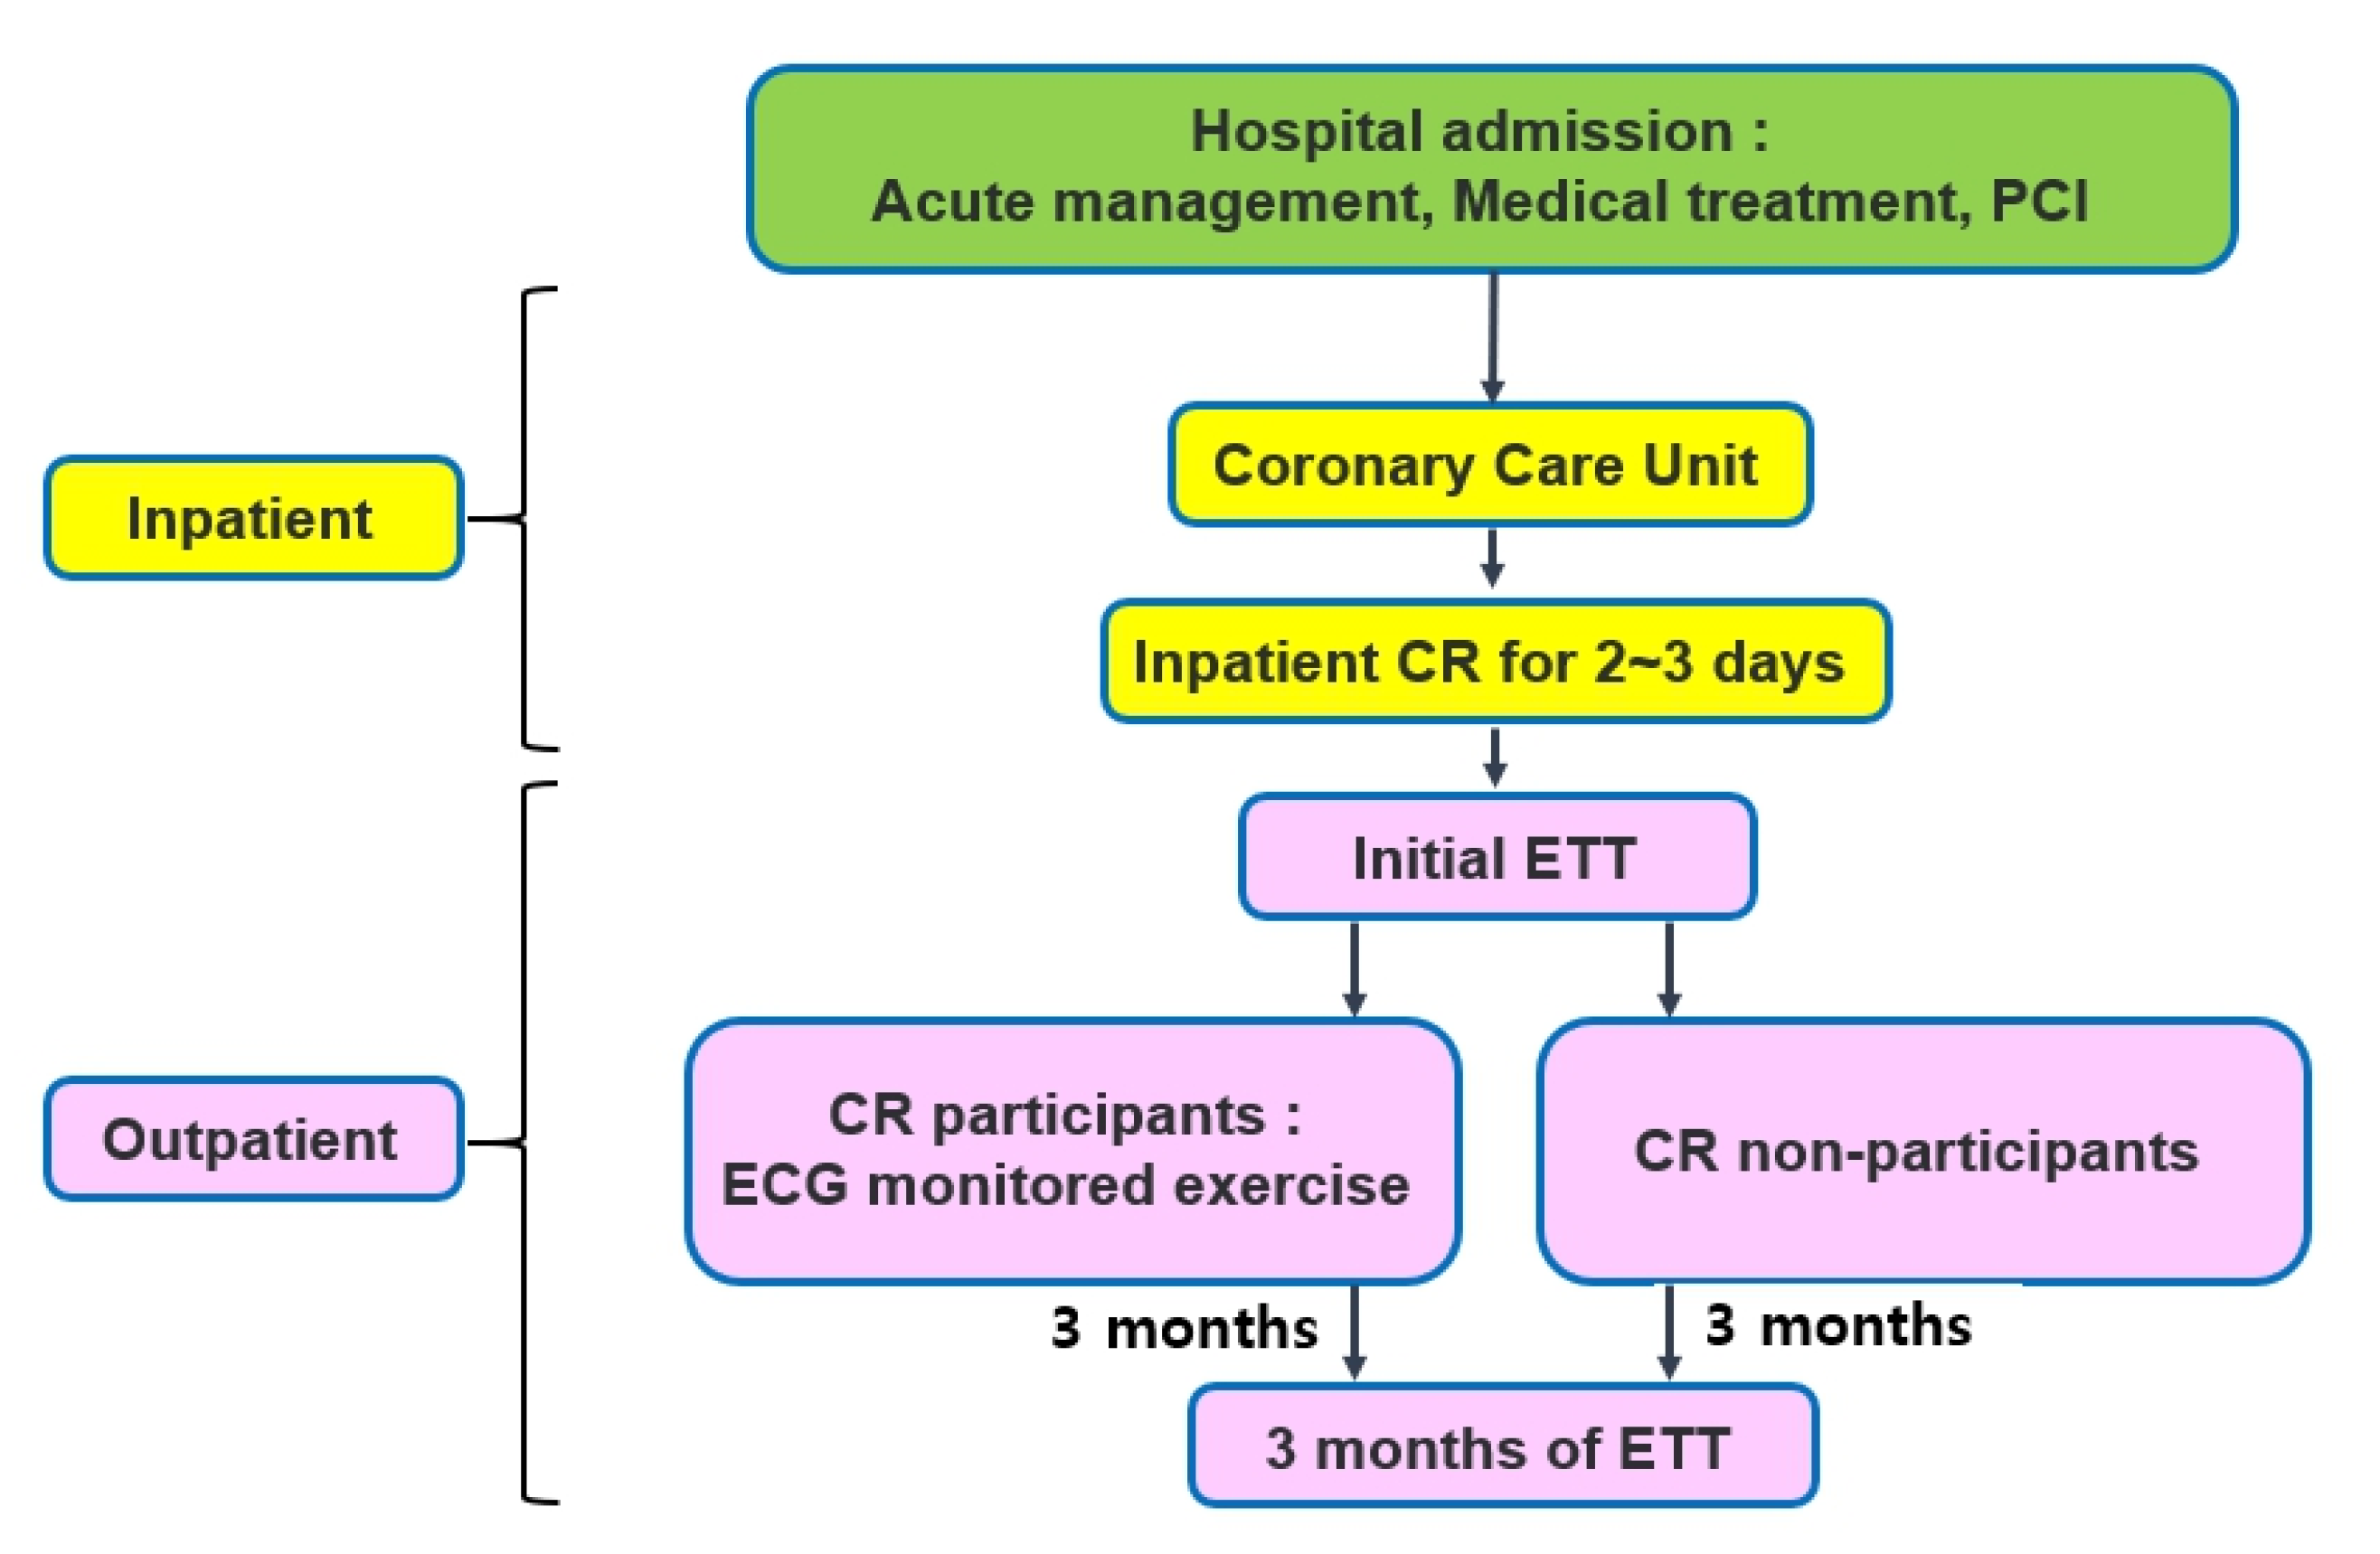

2. Materials and Methods

2.2. Data Abstraction

2.3. Exercise Tolerance Test

2.4. Echocardiography

2.5. Statistical Analysis

3. Results

Demographic Characteristics